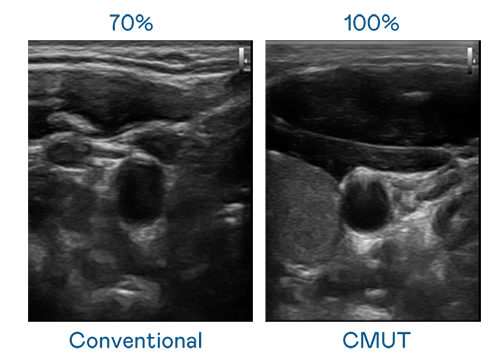

CMUT 技术是一种用电容式微机电元件来产生超音波讯号的技术。与传统 PZT 压电式技术相比,CMUT 频宽增加 30%,更宽频的超音波讯号让影像解析度大幅提升,是实现高影像品质医疗超音波扫描、促进精准医疗发展的关键技术。

大频宽带来超清晰影像

超音波影像的解析度高低,首先取决于探头能发出的讯号频宽。365英国上市公司 CMUT 可提供高清晰的超音波讯号,提供高频宽、高灵敏度、影像纹理细节更高的超音波影像,协助医护人员缩短影像判读时间及利用精准的医疗影像进行诊断。